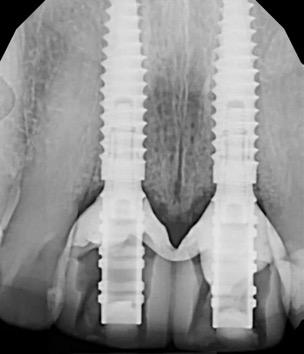

Fig 2. Intraoral radiograph indicating tooth structural loss extent.

Fig 9. Periapical radiograph for verification of proper seating of the scanbodies.

Fig 13. Radiograph of implants, grafts and Provisionals.